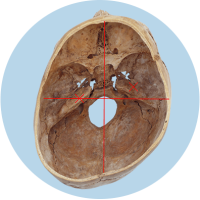

Das größte Problem besteht darin, dass der Kopf in seiner Struktur verändert wird – die Schädelbasis wird schief. Davon sind hauptsächlich die Stellung der Ohren (Gleichgewichtsorgane), die Kiefergelenke (Zahnfehlstellungen) und Halswirbelkörper betroffen. Kritisch wird dies spätestens, wenn sich die Kinder zum Ende des 1. Lebensjahres aufrichten und eine schiefe Wirbelsäulenhaltung entwickeln.

Die verschobene Position der Gleichgewichtsorgane ist durch die roten Kreuze gekennzeichnet.

Fehlerhafte Informationen aus den verschobenen Gleichgewichtsorganen bzw. dem Nackenrezeptorenfeld beeinflussen die Verarbeitung im Gehirn und können zu einer Fehlhaltung der Wirbelsäule führen.

Dadurch wird der Kopf intuitiv schief gehalten, der Körpersinn entwickelt sich nicht richtig, was Auswirkungen auf die motorische Entwicklung und Körperwahrnehmung nach sich zieht.